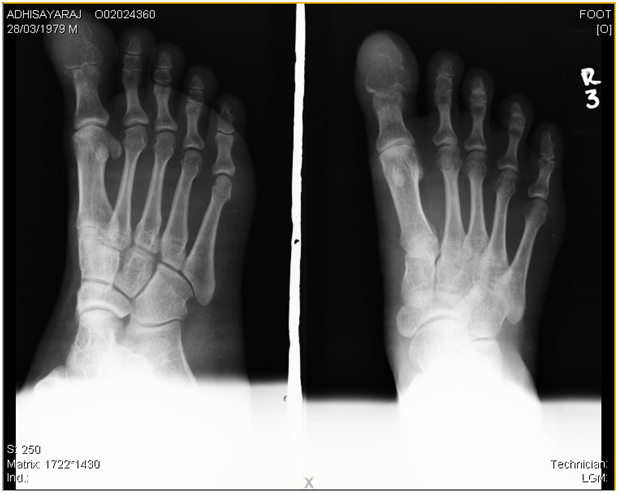

A 30year old male had presented to us with pain and swelling of right big toe of one year duration. The swelling was gradually increasing in size. The swelling was associated with pain. There was no other swelling anywhere else in the body. No constitutional symptoms. On examination there was diffuse swelling of the great toe. Skin was stretched and shiny. There were no engorged veins. The swelling was variable in consistency. The movement of interphalangeal joint was restricted. The x-ray showed an osteolytic lesion involving the distal phalanx. The cortex was eroded and lesion was extending into the soft tissue. The routine blood investigations were normal. Serum alkaline phosphatase level was normal. We had a differential diagnosis of giant cell tumor and bone cyst. We had done excision of the distal phalanx. Since the lesion was extending into the soft tissue we had planned for a radical excision. The biopsy showed giant cell tumor of the distal phalanx. Regular follow up of the patient showed no recurrence of the tumor.

The standard treatment of this tumor has traditionally been intra lesional excision, aggressive curettage with or without bone grafting. The recurrence rates are high after this procedure. The recurrence of tumor has been reduced, by using chemical or physical means of inducing necrosis of any remaining neoplastic tissue. The other surgical option is en-bloc resection of involved bone segment. We choose the last option for this patient because of aggressive features of the lesion. Giant cell tumour involving the phalanx in foot is very rare. These are aggressively growing tumors. Giant cell tumor in such a location need regular follow to detect local recurrence (Figure 1).

Figure 1 cell tumour of phalanx of great toe.